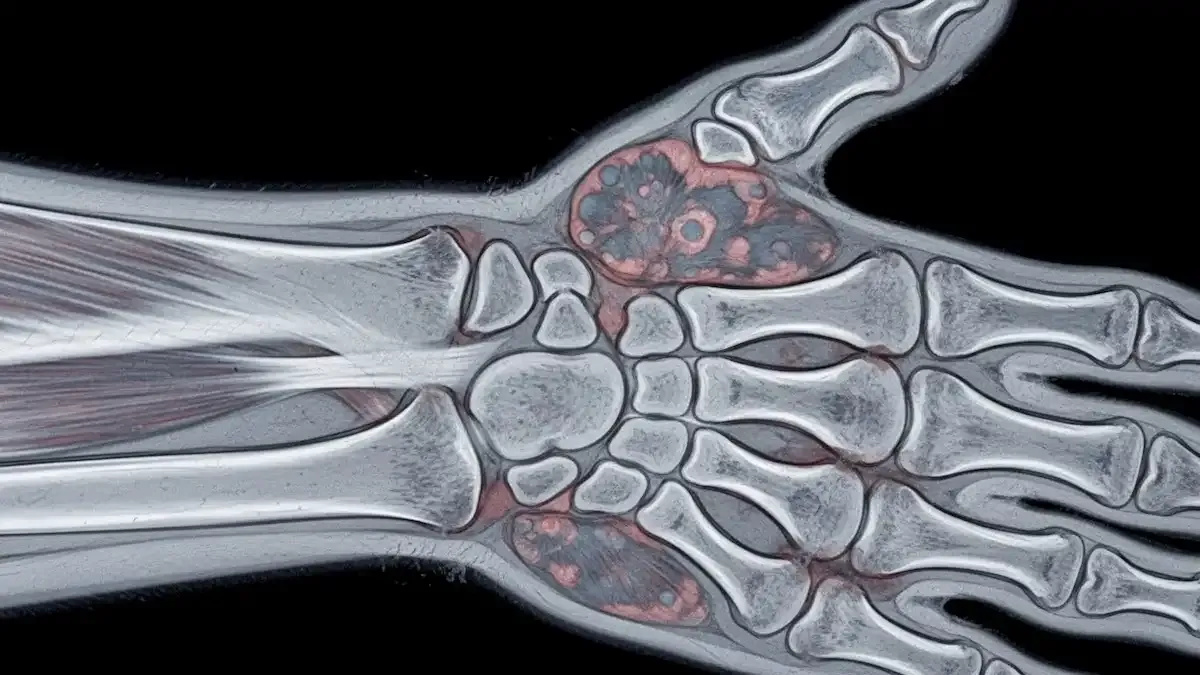

Como Saber Se Desloquei O Dedo Da Mão?

Lesões nos dedos são frequentes no consultório, principalmente após quedas, impactos ou atividades esportivas. Muitos dos meus pacientes ficam na dúvida: como saber se desloquei o dedo da mão? A luxação acontece quando os ossos da articulação saem...